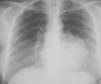

A chest X-ray (Fig. 1) showed a hilar and paracardial left opacity with a well defined border and internal margin which extended into the mediastimum.